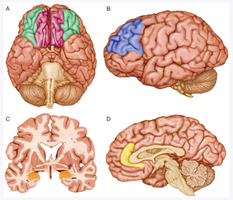

Historical treatments included trepanation (drilling holes in the skull to release 'evil spirits') and the establishment of asylums.